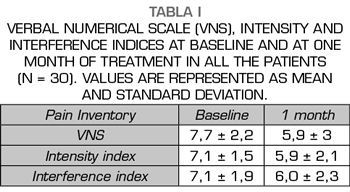

Results: The VNS score decreased from 7.7 ± 2,2 to 5.9 ± 3 (p < 0.01). Intensity and Interference Scores were reduced from 7.1 ± 1.5 to 5.9 ± 2.1 (p < 0.01) and 7.1 ± 1.9 to 6.0 ± 2.3 (p < 0.02) respectively. In 12 patients (40 %) a satisfactory analgesic response was observed. In these patients the VNS decreased from 8.0 ± 1.5 to 3.8 ± 2.6. Intensity and Interference Scores were reduced from 7.4 ± 1.3 to 3.9 ± 1.5 (p < 0.0001) y 7.7 ± 1.9 to 4.9 ± 2,7 (p = 0.002) respectively.

The score in the VNS prior to the procedure was reduced from 7.7 ± 2.2 to 5.9 ± 3 (p <0.01, t test for paired samples), taking into account the entire sample (n = 30), which implies a variation of 23% (Table I, Figure 3). The Intensity Index decreased from 7.1 ± 1.5 to 5.9 ± 2.1 (p <0.01), which implies a change of 16%, while the Interference Index decreased by 15% (7.1 ± 1.9 to 6.0 ± 2.3) (p <0.02) (Table I, Figures 4 and 5). When evaluating the patients who responded favorably using VNS, 12 out of 30 patients showed a decrease of at least 2 points on that scale, representing 40% of the sample. If we analyze these patients separately, we can observe that the initial values of VNS decreased from 8.0 ± 1.5 to 3.8 ± 2.6 after the procedure, which implies a reduction of 53% (Table II, Figure 6).

In eight patients with a satisfactory outcome after one month, a three-month evaluation of the procedures was conducted. In these, the VNS remained at low values, 3.8 ± 3.3 (p = 0.007), something similar happened with the Intensity and Interference Indexes, being 4.3 ± 1.6 and 5.4 ± 2.5, respectively (p = 0.001 and p = 0.02, when compared with the baseline values (Figures 6, 7 and 8).